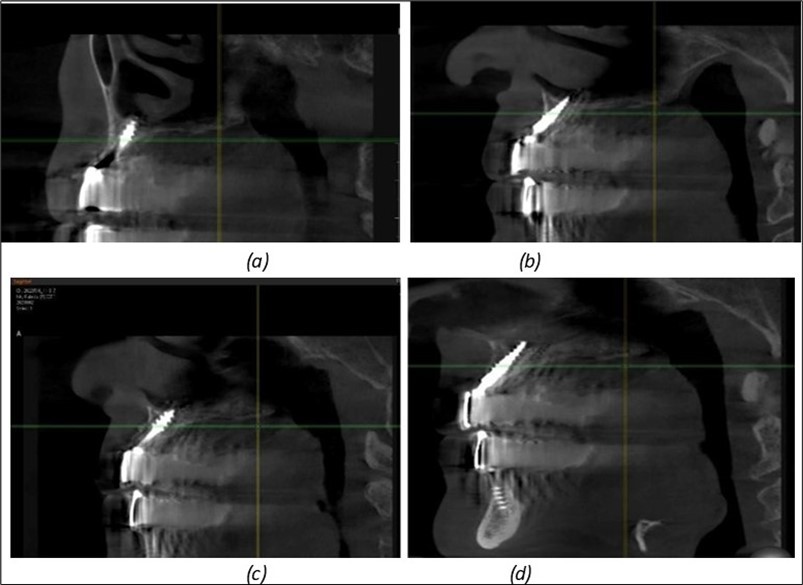

Figure 8.(a), (b) Sinus lift and grafting area with two stage implants before their removal. (c) area of fixation of BCS and TPG implants, avoiding the sinus lift and grafting area

Figure 9.Implants in the pterygoid plateau area: (a) TPG implant fixed in the maxillary-sphenoid junction area, quadrant 1; (b) TPG implant fixed in the maxillary-sphenoid junction area, quadrant 2.

Figure 10.Implants in the palatal sinus cortical area to avoid bone grafting: (a) BCS implant partially fixed in the graft material mass, partially in the palatal cortex; (b) Implant fixed in the palatal cortex at the junction with the nasal cortex, behind the graft material mass.

Figure 11.Implants in the anterior area anchored in the nasal cortex (BCS and TPG): (a), (c) – BCS implants fixed in the nasal cortex; (b), (d) – TPG implants fixed in the second nasal cortex with compression in the trabecular area.

Figure 12.Implants fixed distally in quadrant 4 with fixation at the level of the mylohyoid line: (a) The most distal implant fixed in unaffected bone from the previous restoration; (b) The implant fixed in the area where the two stage implant was removed.